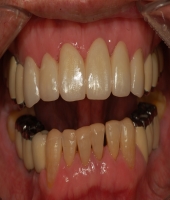

| ● 진료과목 : [임플란트] 틀니 사용중, 임플란트로 교체하기

| ● 내용 : 하악틀니 사용 중 불편감으로 임플란트로 교체한 예 |